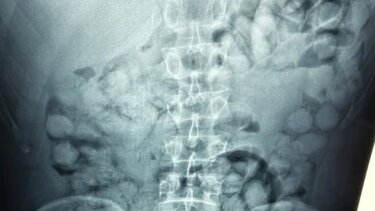

Ένας άνδρας, από τη Βραζιλία, συνελήφθη σήμερα το πρωί στο αεροδρόμιο «Ελ. Βενιζέλος», κατηγορούμενος ότι είχε καταπιεί σημαντική ποσότητα κοκαΐνης.

Σύμφωνα με την ΕΛΑΣ, ο άνδρας έφτασε στην Αθήνα, μέσω Παρισιού και στον έλεγχο που διενεργήθηκε, διαπιστώθηκε ότι είχε καταπιεί περίπου 100 συσκευασίες κοκαΐνης.